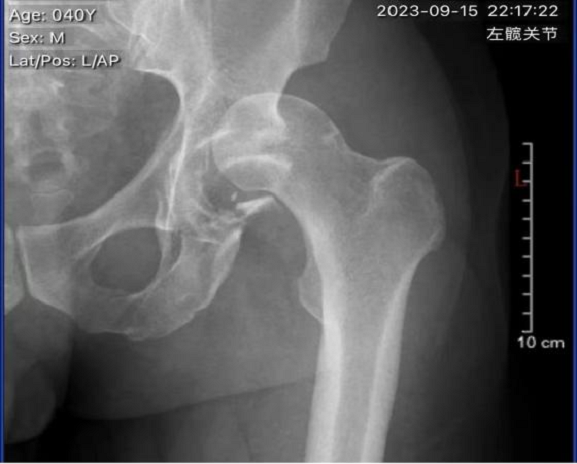

二、骨折情况

骨科医生团队:张卫、齐玉疆、余祥卫